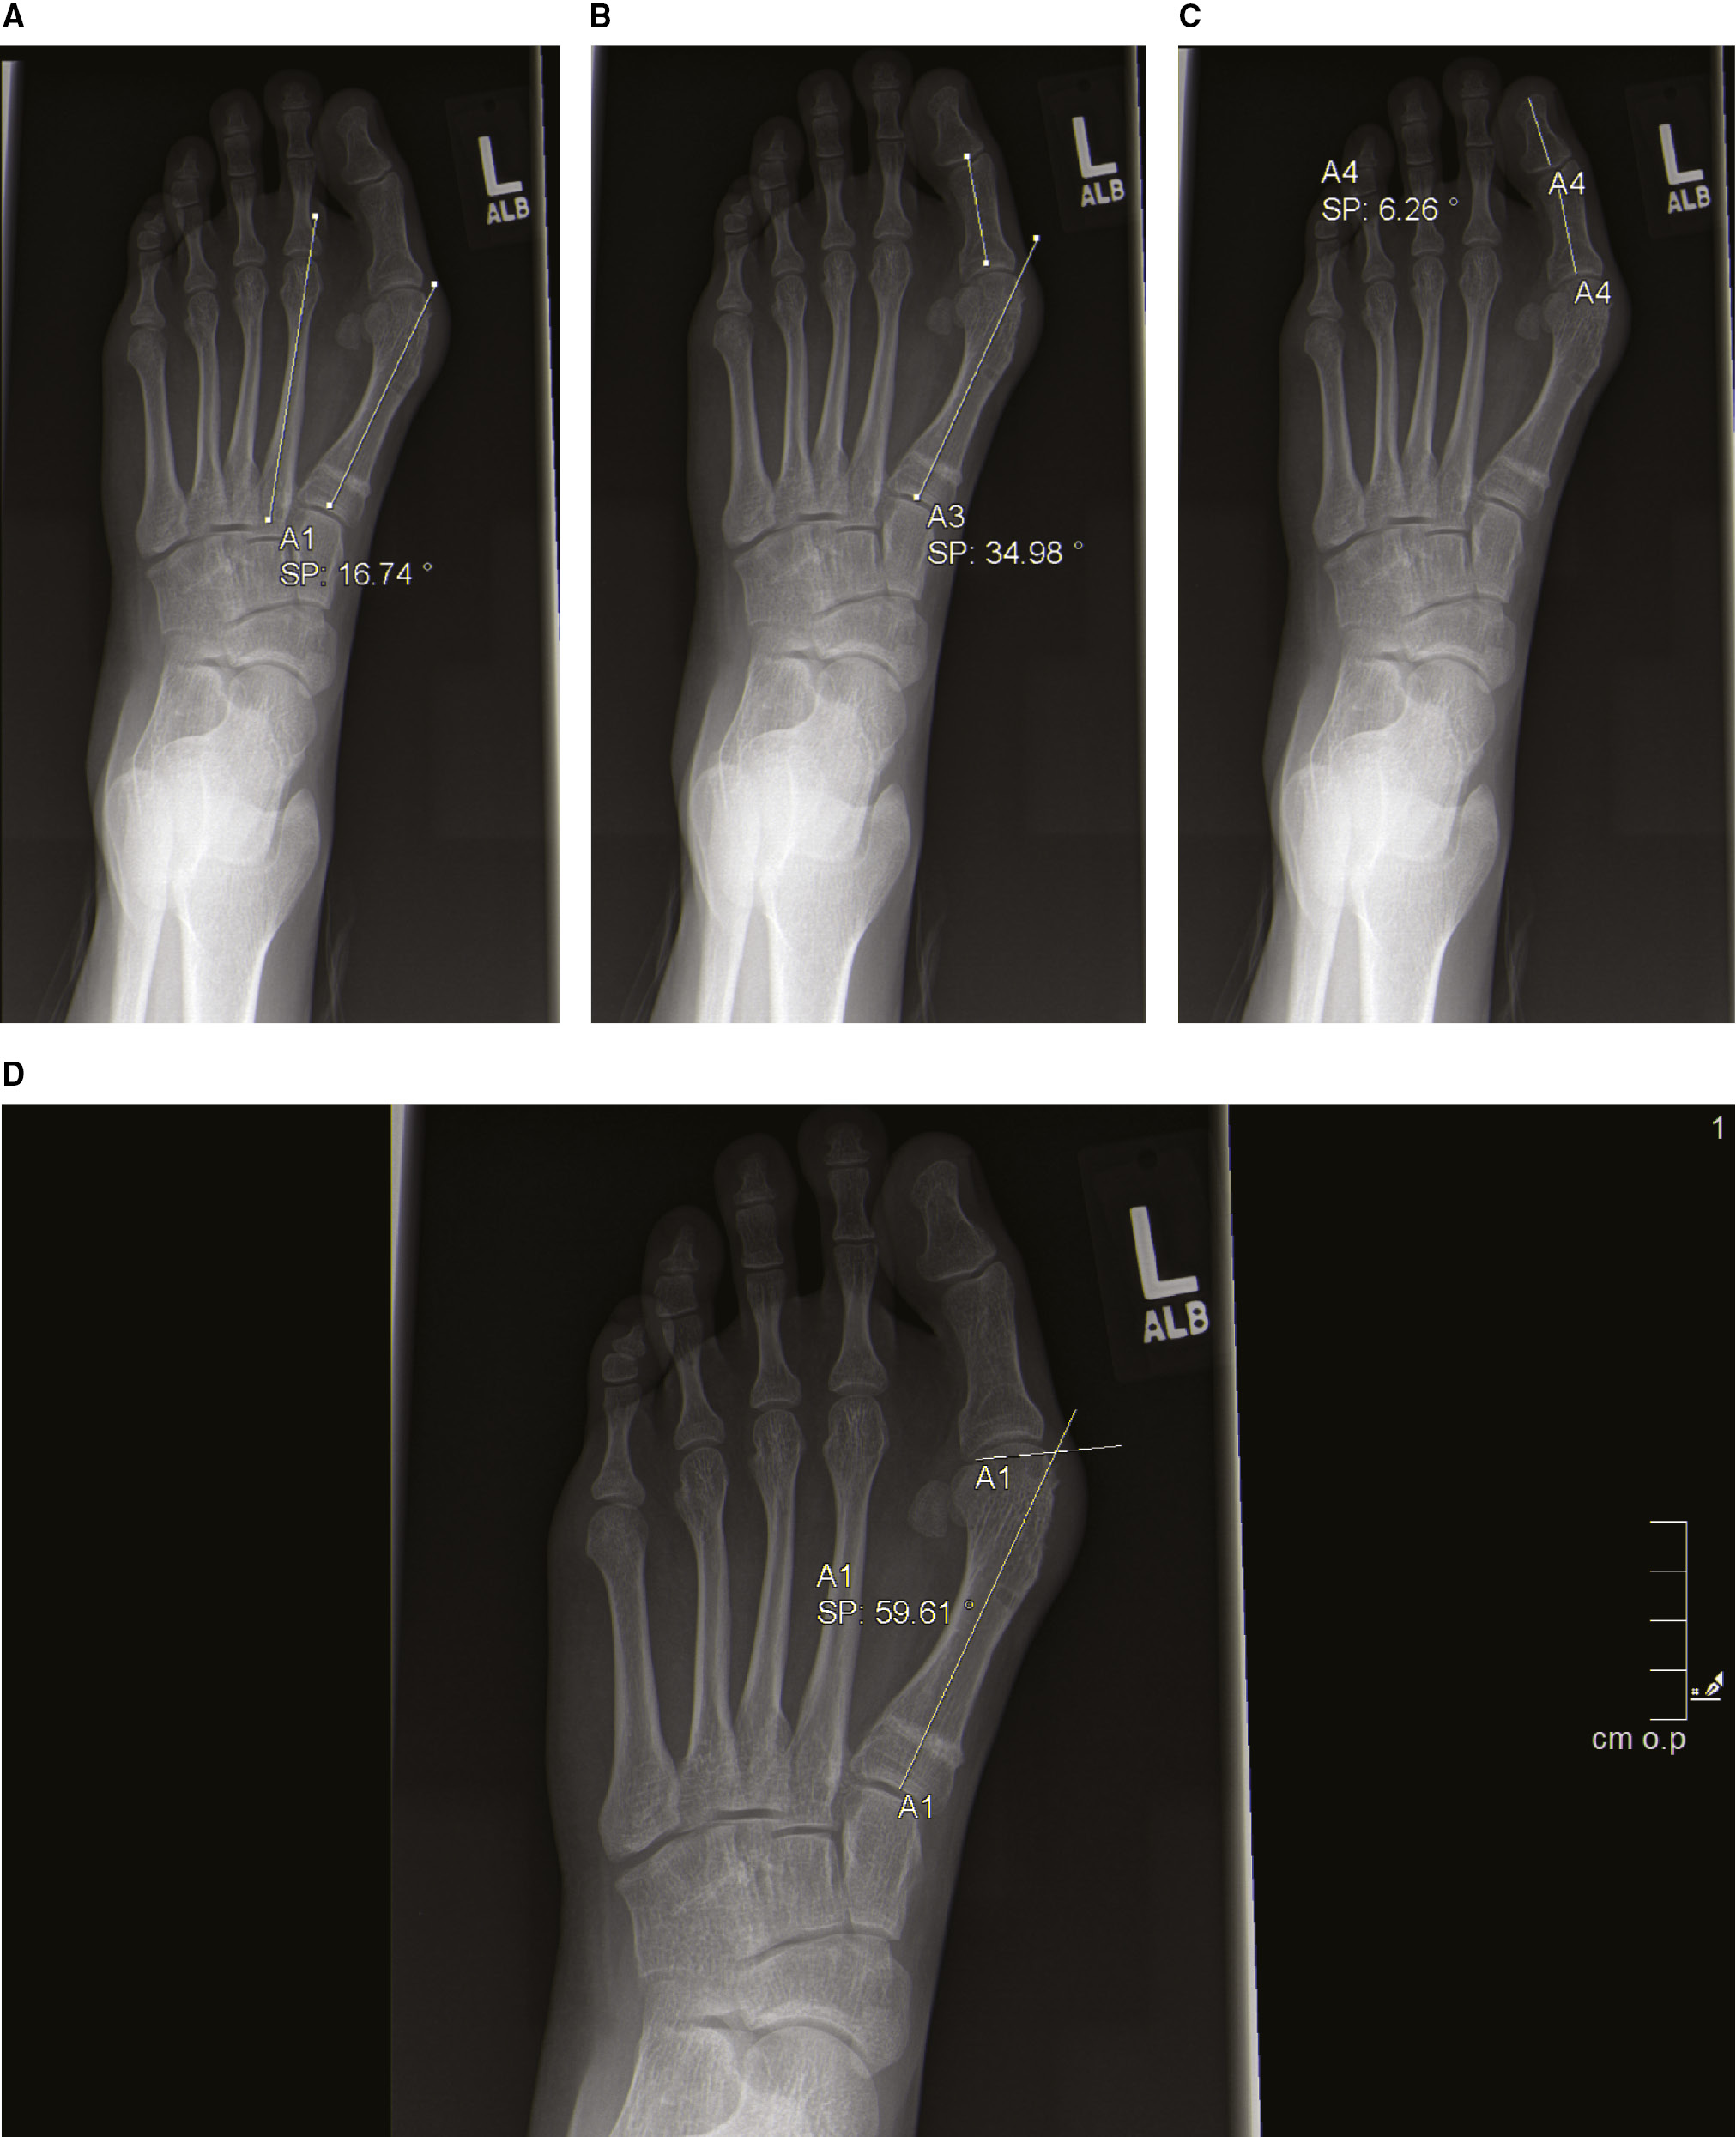

Standing radiographs of the foot are obtained. On the anteroposterior (AP) radiograph, the 1st/2nd intermetatarsal angle (IMA), the hallux valgus angle (HVA), the distal metatarsal articular angle (DMAA), and the angle between the proximal and distal phalanx are measured (Figure 1). No specific degree of interphalangeous deformity delineates the need for treatment, and it is difficult to predict those that will require treatment based on preoperative radiographs secondary to the pronation. Furthermore, the authors do not advocate for a specific DMAA cutoff in decision-making, as the preoperative DMAA measurement may be unreliable given the rotation of the metatarsal. Further guidance on the management of these scenarios is detailed in the Operative Technique.

Figure 1. Preoperative radiographic assessment of a 15-year-old female with recurrent adolescent hallux valgus after proximal 1st MT opening wedge osteotomy and distal soft tissue realignment. (A) Intermetatarsal angle (IMA). (B) Hallux valgus angle (HVA). (C) Angle between the proximal and distal phalanges. (D) Distal metatarsal articular angle (DMAA).

The obliquity of the TMTJ and the location of the medial and lateral sesamoids is noted. Make note of the thickness of the cortex of the 2nd metatarsal (Figure 2). Patients with hypermobility of the 1st ray may be transferring more stress to the 2nd metatarsal, leading to hypertrophy. On the lateral radiograph, note the talar/1st metatarsal angle to evaluate for planus and look for plantar gapping of the 1st TMTJ.